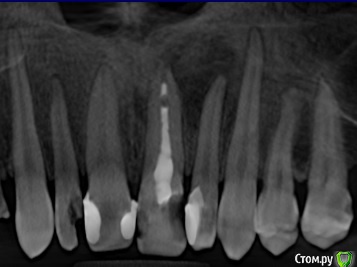

shishok Опубликовано 30 сентября, 2017 Поделиться Опубликовано 30 сентября, 2017 Лечить,вероятнее всего,придется два зуба(21 и 22). Ссылка на комментарий

DmitrySH Опубликовано 10 октября, 2017 Поделиться Опубликовано 10 октября, 2017 Если уж зашла речь как по вашему от чего у меня образовалась полость ? Некачественная работа или материал ? Могут быть разные причины.. Гибель пульпы в зубе 22 из-за глубокой кариозной полости, нарушение герметизма корневого канала в зубе 21 и тп. Снимок 2010 года было бы интересно посмотреть. 1 Ссылка на комментарий